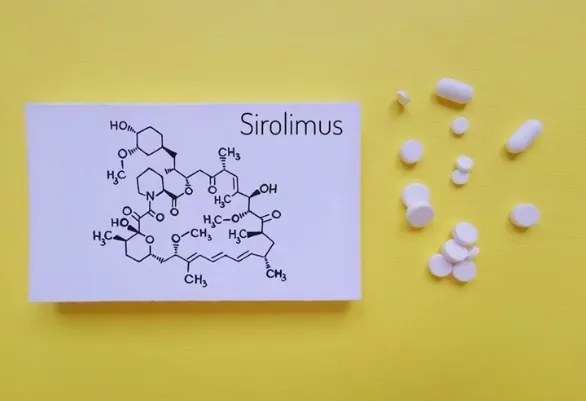

Você sabia que injeções cosméticas podem causar hipercalcemia e insuficiência renal anos após o procedimento? Descubra mais sobre os riscos e tratamentos dessa complicação em nosso novo post no blog!